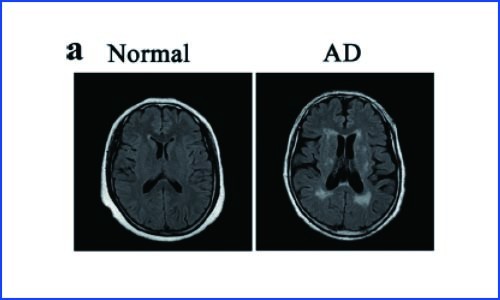

文献解读 | scRNA-seq 揭示了与阿尔茨海默症 B 细胞相关的生物标志物